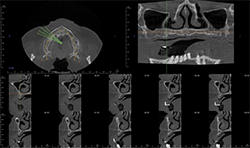

Fig. 2A

Fig. 2B

Fig. 2C

CBCT images of the same patient (Figs. 2A, 2B, 2C) reveal the lesion extends mesial to the third molar follicle, displacing the thinning buccal cortex. The lesion arises from the cementoenamel junction (CEJ) of the second molar. The inferior alveolar nerve canal is intact. The lesion was treated by surgical removal and submitted for histological examination. The histopathologic diagnosis was a dentigerous cyst.